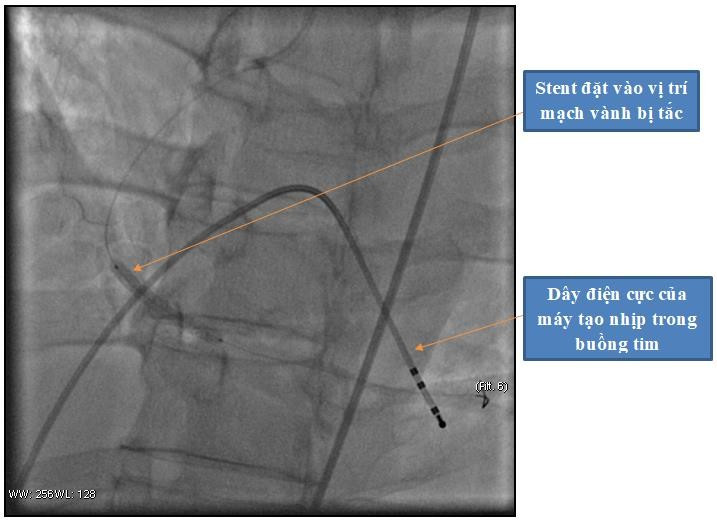

Ê - kíp can thiệp đã tiến hành đặt máy tạo nhịp tim cho người bệnh và đặt 1 stent vào vị trí bị tắc. Sau khi can thiệp đặt stent, động mạch vành đã được tái thông - Ảnh BVCC

Có lại nhịp tim mới chỉ là bước đầu. Tình trạng của người bệnh vẫn đang “ngàn cân treo sợi tóc” vì nguyên nhân gây ngừng tim là do nhồi máu cơ tim vẫn còn đó, tim có thể tiếp tục ngừng đập bất kỳ lúc nào. Người bệnh nhanh chóng được chuyển vào phòng can thiệp tim mạch để chụp và can thiệp mạch vành tái thông mạch vành bị tắc.

Tại phòng can thiệp các bác sĩ đã tiến hành Chụp động mạch vành cho kết quả: động mạch vành phải bị tắc hoàn toàn. Do thời gian ngừng tuần hoàn quá dài, người bệnh rơi vào tình trạng suy đa tạng, tình trạng sốc tim và rối loạn nhịp tim vẫn còn. Sau can thiệp, người bệnh được chuyển về Khoa Hồi sức tích cực – Chống độc để điều trị hồi sức chuyên sâu.